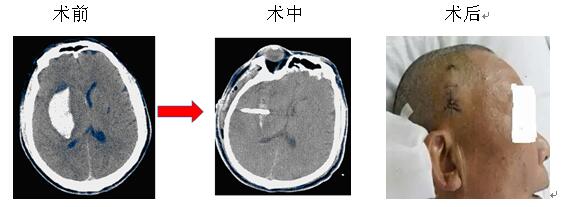

微創(chuàng)治療腦出血是指在CT或立體定向引導(dǎo)下,找到離血腫中心最近的位置,同時避開重要的組織,用YL-I型針管一體裝置在電驅(qū)動下安放引流管、抽吸血凝塊,減少血腫體積,達(dá)到清除血腫的目的。此方法創(chuàng)傷微小,操作快捷,費(fèi)用較低,在有CT的醫(yī)療器械情況下即可實施,故對廣大病患,特別是老年多病的腦出血患者而言是一種不二的選擇。

院神經(jīng)內(nèi)科率先在衡陽地區(qū)實施微創(chuàng)治療腦出血,現(xiàn)經(jīng)救治的病患已達(dá)3000余人次,絕大部分患者得到好的結(jié)果,較少的死亡率,較輕的致殘率。本院將繼續(xù)提供較好的治療和服務(wù),來滿足病友的需求,也歡迎病友垂詢。